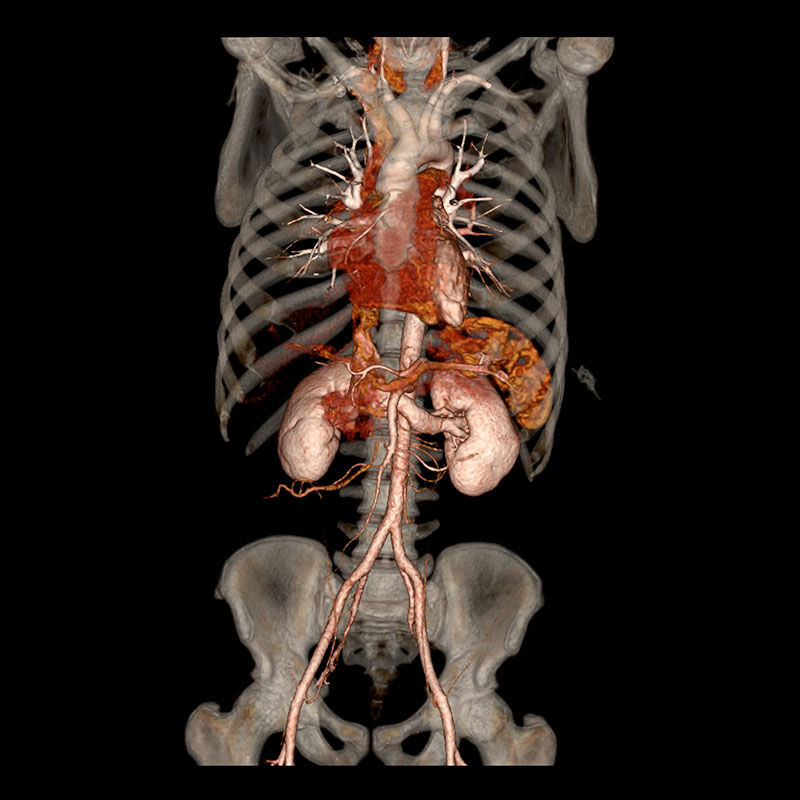

CT SCAN

img01

CT-Scan Aquilion Prime SP

• Comfortable & Fast Experience

Wide 78 cm open design and extremely fast scanning reduce stress, breath-holding, and discomfort — perfect for children, elderly, and nervous patients.

• Low Radiation for Your Safety

Advanced dose-reduction technology keeps radiation as low as possible while still delivering clear, reliable images.

• Clear & Accurate Results

High-resolution, 160-slice imaging provides sharp detail for chest, abdomen, brain, spine, blood vessels all angiographic studies (Coronary Angio) CALCIUM SCORE, full-body assessments and stroke evaluation.

• Ideal for All Patients

Comfortable for larger or mobility-impaired patients thanks to the wide opening and quick exam times.

• Great for Emergency & Routine Scans

Captures fast, precise images for trauma.

• Smooth, Quick Visit

High-speed imaging means less time on the table and faster results for your doctor.

• Vitrea post processing AI software

Multi-planer reformatting (MPR), 3D and 4D Advanced visualization, Quantitative analysis and measurement tools (Calcium score), Reduce noise and artifact.